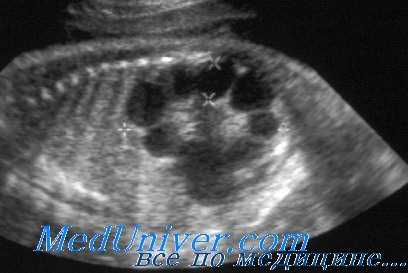

(Слева) УЗИ во фронтальной плоскости. Не совсем типичная ультразвуковая картина. Почки крупные, гиперэхогенные, содержат гипоэхогенные пирамиды. Умеренное расширение лоханки. При прогрессировании заболевания картина может измениться.

(Справа) Тот же случай. Постнатальное УЗИ во фронтальной плоскости. Более типичная картина: паренхима диффузно гиперэхогенная, утрачена нормальная структура мозгового вещества. Данный случай иллюстрирует разнообразие ультразвуковых находок при АРПКП.

(Слева) Другой случай АРПКП. УЗИ в сагиттальной плоскости. Визуализируются увеличенные гиперэхогенные почки (калиперы). Нормальная гипоэхоген-ная кора сохранена. Это довольно характерная находка, но обнаружить ее на пренатальном УЗИ бывает трудно.